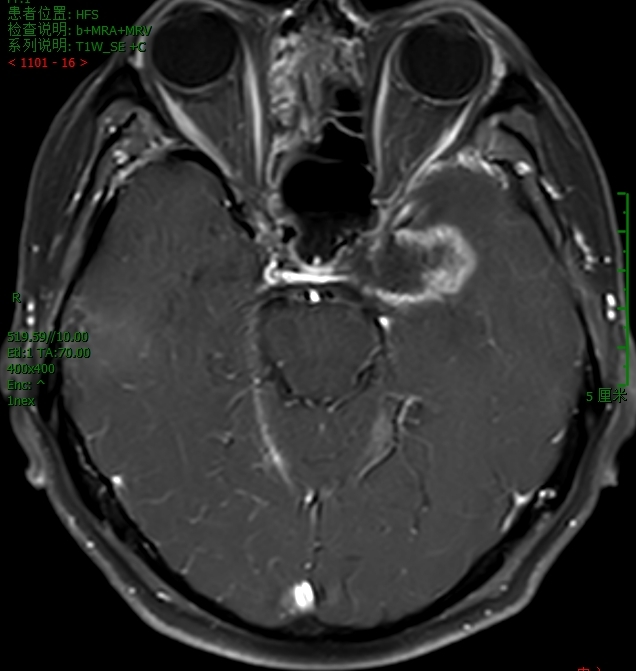

我院PET-CT检查显示鼻咽周围骨质改变,未见异常代谢增高,无肿瘤复发;左侧颞叶、左侧岛叶及左侧鞍旁片状低密度影,伴代谢稀疏,提示放射性坏死。脑室造影检查显示颅内积气,前颅底鞍结节颅骨缺损,脑脊液漏可能(图1-3)。MRI检查显示左侧颞叶内侧面不规则强化病灶,考虑放射性脑坏死改变(图4)。